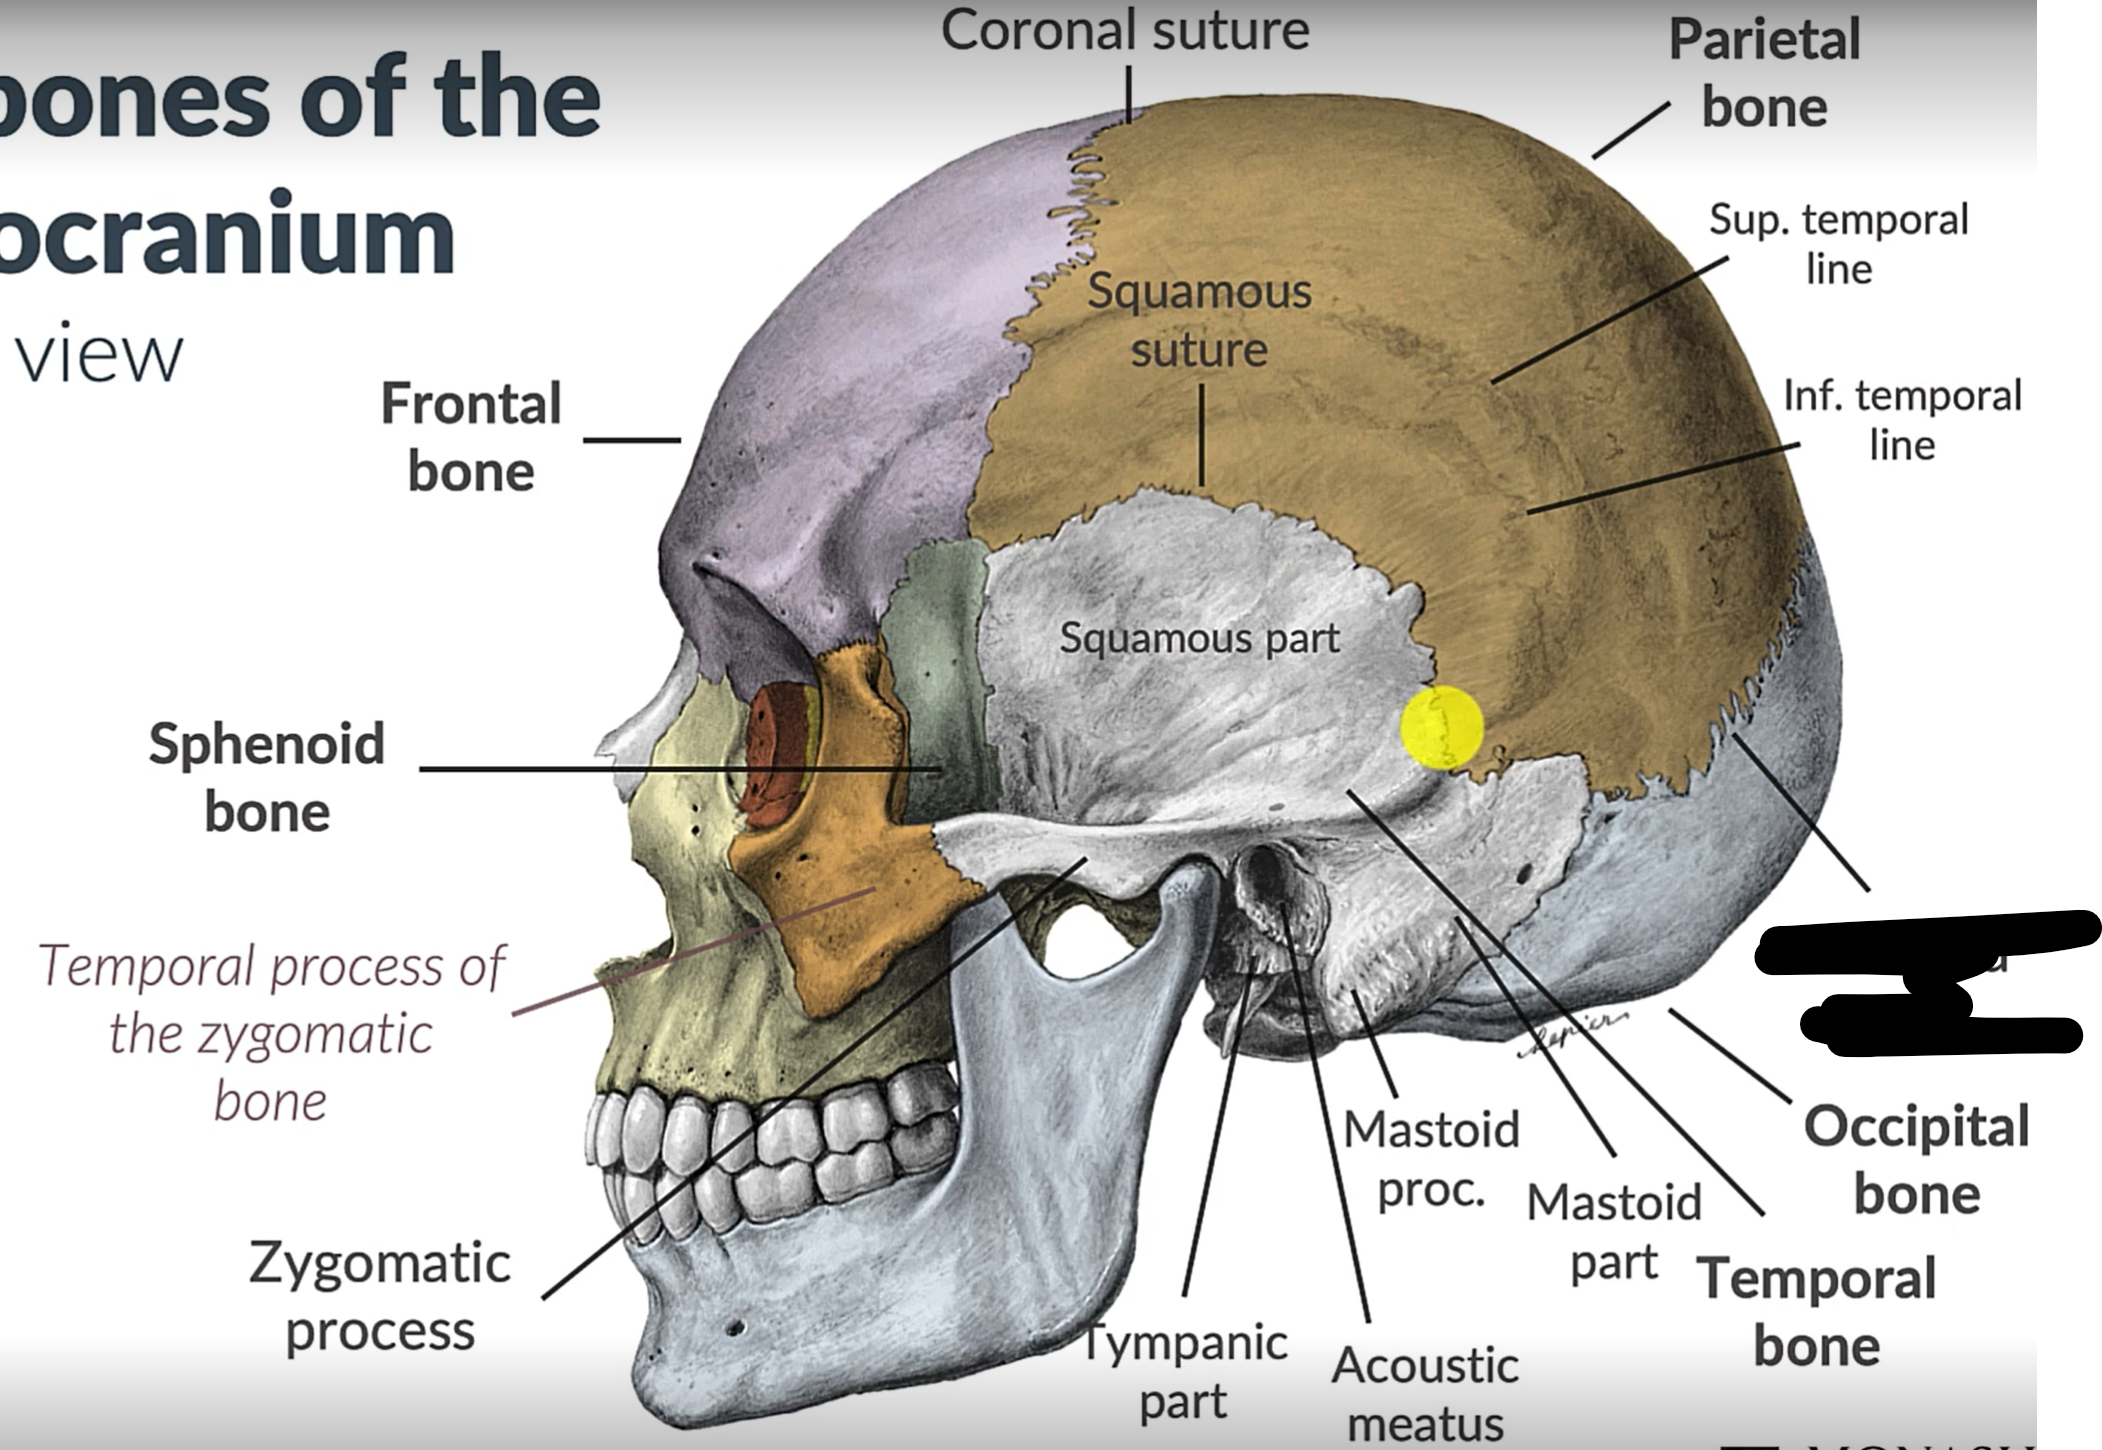

What bones make up the neurocranium?

Occipital bone (1)

Parietal bones (2)

Frontal bone (1)

Temporal bones (2)

Sphenoid (1)

Ethmoid (1)

What are the 4 cranial sutures and what do they separate?

Lambdoid - separates occipital from parietal and temporal

Sagittal - extends between parietal bones

Coronal - divides frontal and parietal bones

Squamous - either side of cranium, separates temporal and parietal bones

What is the pterion?

The point where the frontal, parietal, sphenoid and temporal bones meet.

Pterion